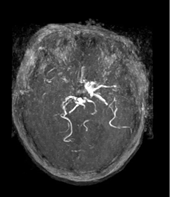

吳老婦人有冠心症、心房顫動、高血壓、高血脂病史,平日有服用抗血小板劑保栓通,她日前中午用餐後突然倒下,出現意識模糊、口齒不清、眼睛往右看,左側手腳都無法動彈,為恭急診室收治,神經內科主任朱清華、醫師卓筱善評估後,診斷是腦部大血管阻塞,電腦斷層血管攝影呈現右側頸總動脈大血管都有血栓,無血流通過。

醫師在老婦人發病2小時內注射血栓溶解劑治療,為恭、雙和醫療團隊進行腦動脈取栓治療抽吸術,抽取12公分的血栓,手術時間約3小時,由於腦血栓清除迅速,病人清醒後能講話,眼球轉動靈活,左側癱瘓的手腳目前在復健進步中。

83歲吳姓老婦人日前中風,電腦斷層血管攝影顯示腦部大血管阻塞,為恭及雙和醫療團隊腦動脈取栓治療抽吸術,抽取12公分的血栓。 |